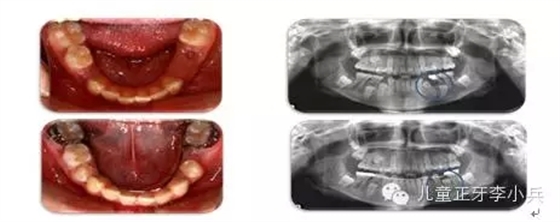

1. 兒童牙病的治療與錯(cuò)合畸形的預(yù)防:兒童齲病造成牙冠橫徑變短、乳牙早失、磨牙前移。兒童根尖周病影響恒牙發(fā)育及萌出異常,阻生。兒童牙病治療、間隙維持能預(yù)防繼承恒牙的萌出異常。(圖2,病例一)

圖2 75深齲,34牙胚萌出異常,拔出75,舌弓間隙維持后,34萌出道自行調(diào)整萌出;